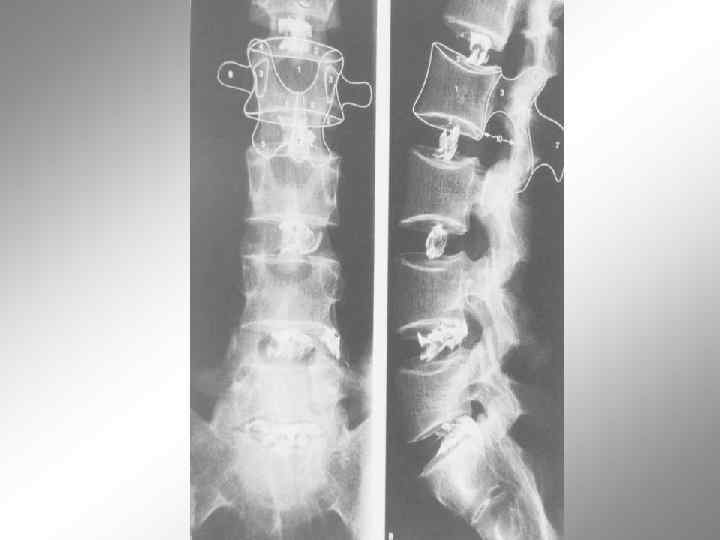

Спондилолиз Спондилолистез

Спондилолистез